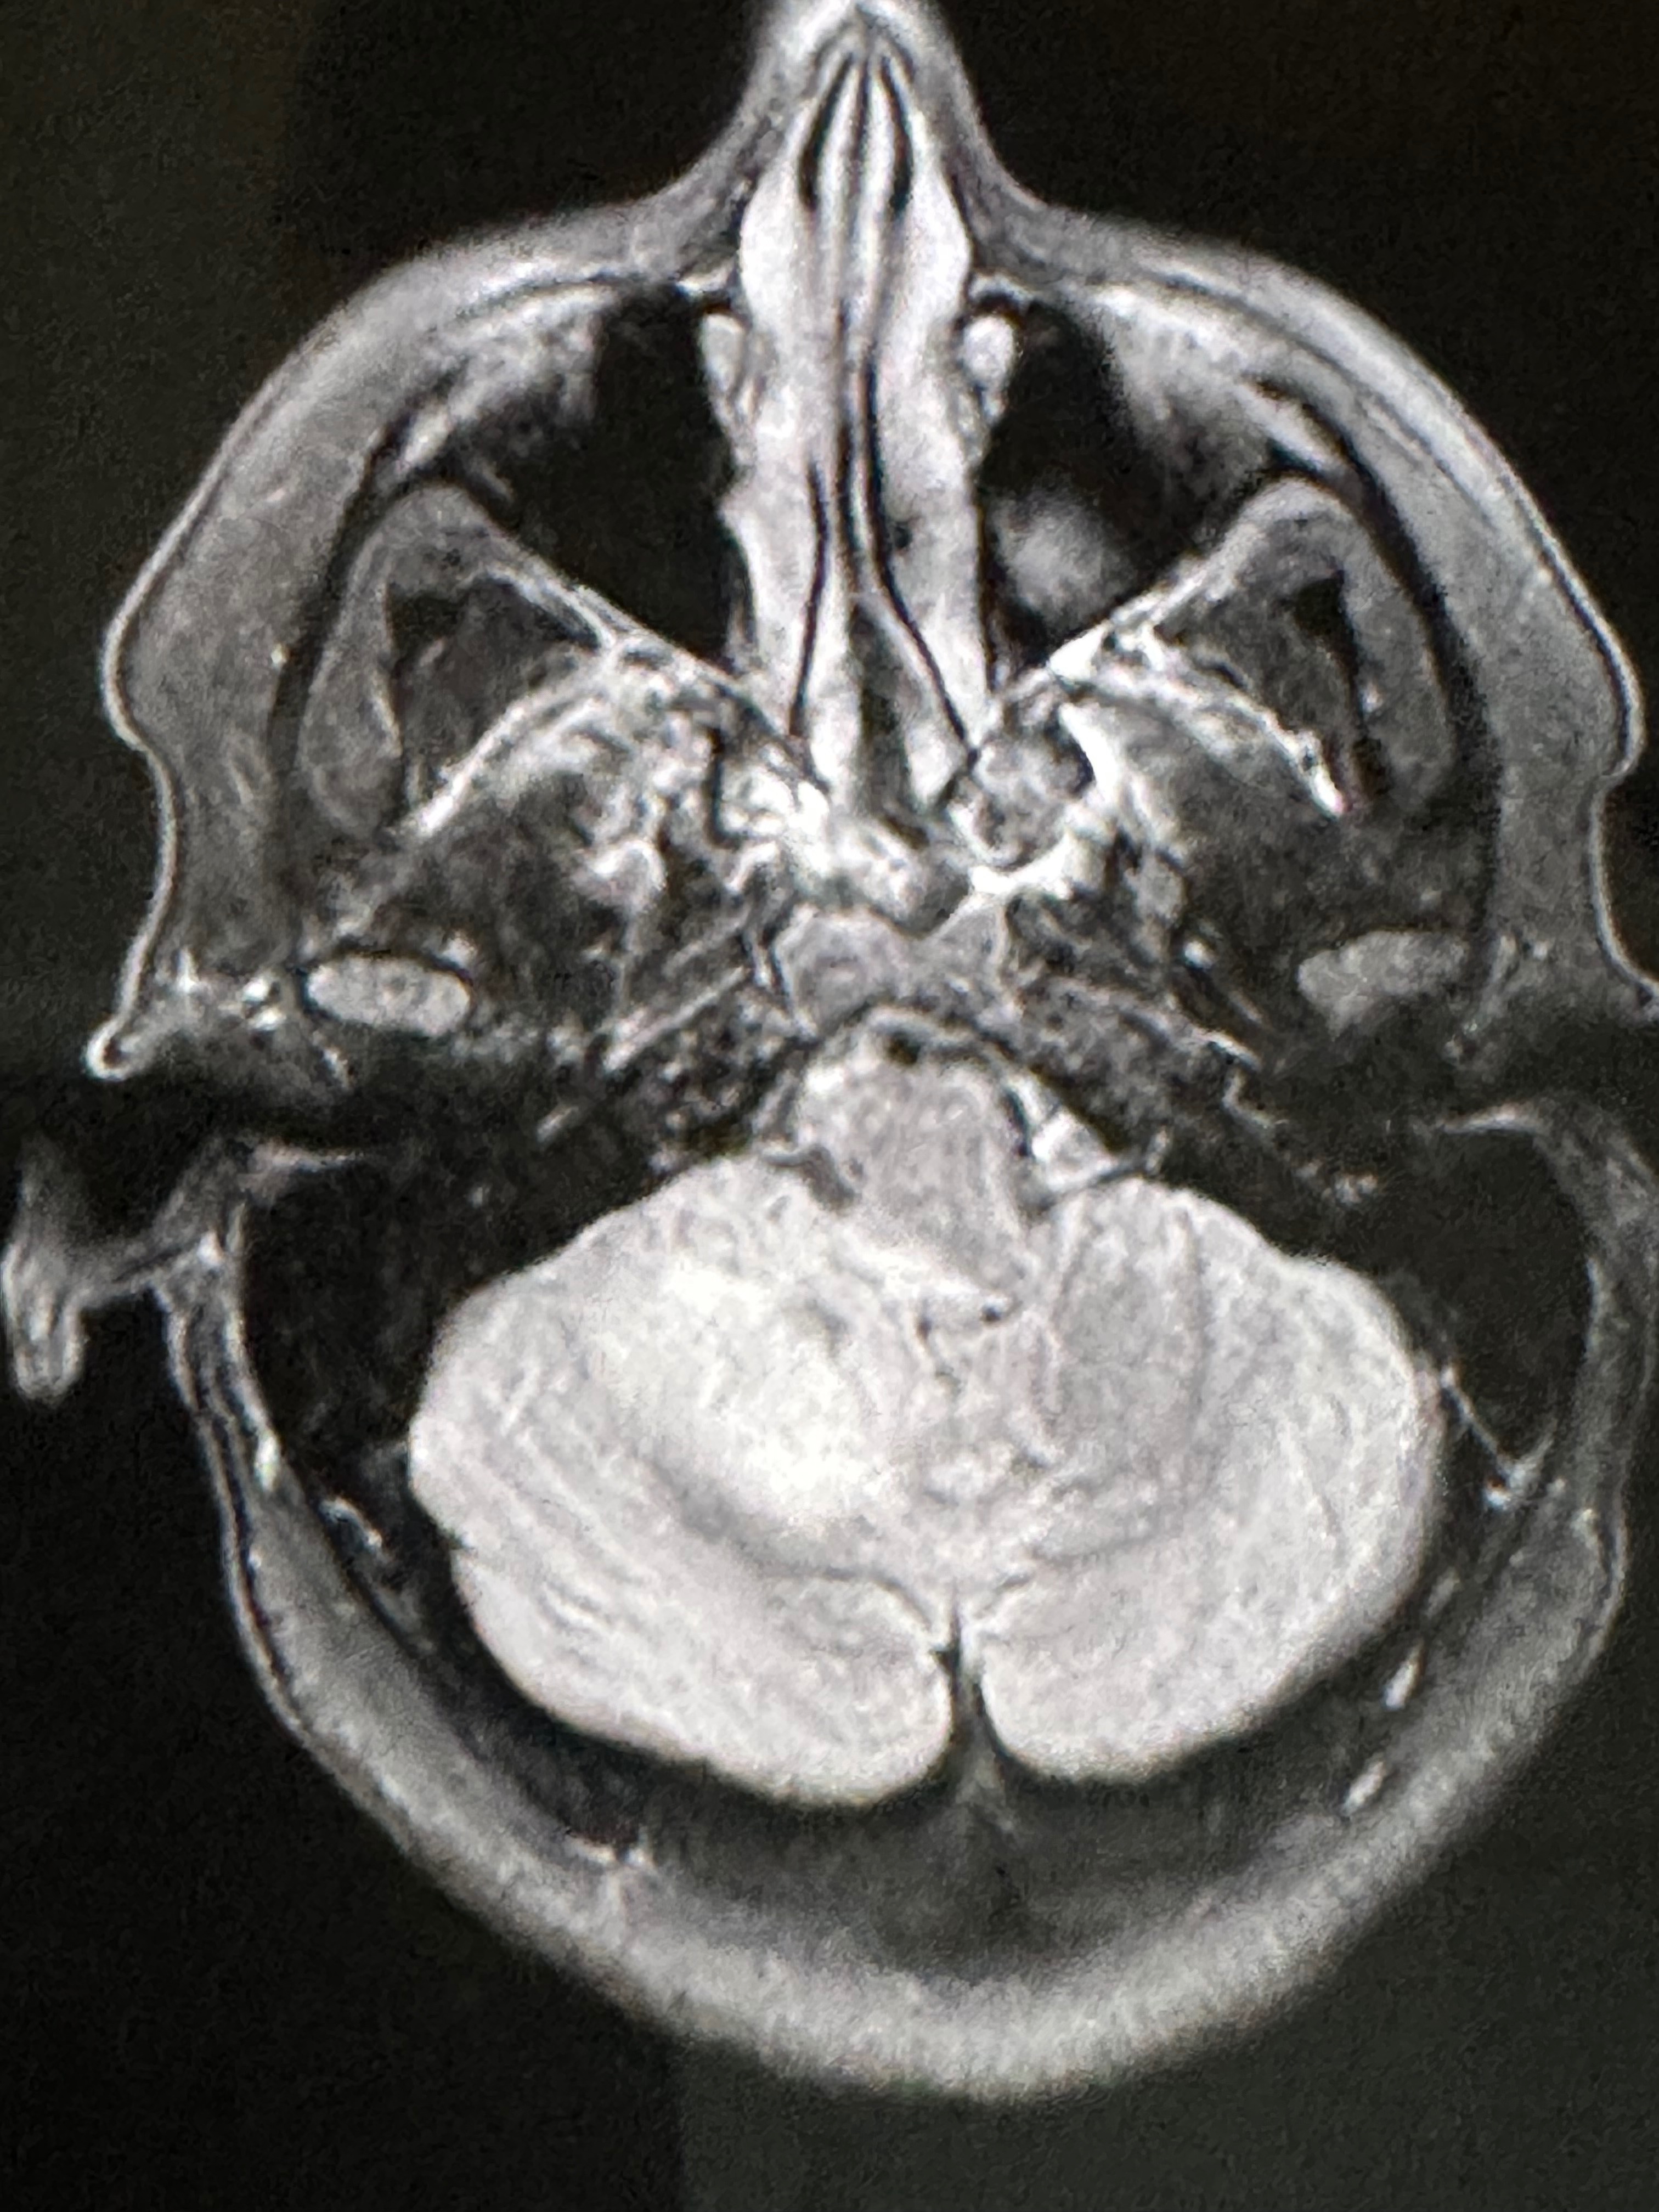

Well, for the ones who don’t know me, I’m Jennifer, mother of 6. Out of nowhere, I ended up sick and went to the emergency room. They told me it was vertigo. A couple of days go by, and I get worse and worse, where I had to call 911 again and end up back in the ER. They ended up doing a CT scan and MRI, and they found a tumor/mass in my brain in the cerebellum. I got admitted to the hospital for two weeks, where they said my brain on the right side was too swollen, and they couldn’t do anything due to where the tumor is at. So, they put me on steroids. I also got sent home after the two weeks on the steroids. After one week and a half, I finished all the steroids. I started to get pain again in my head, where medicine wasn’t helping, so I ended up back in the hospital and got admitted again. They did 3 more MRIs and a spinal fluid test to see if they could find out what it could be. I have 3 more tests that need to be done.